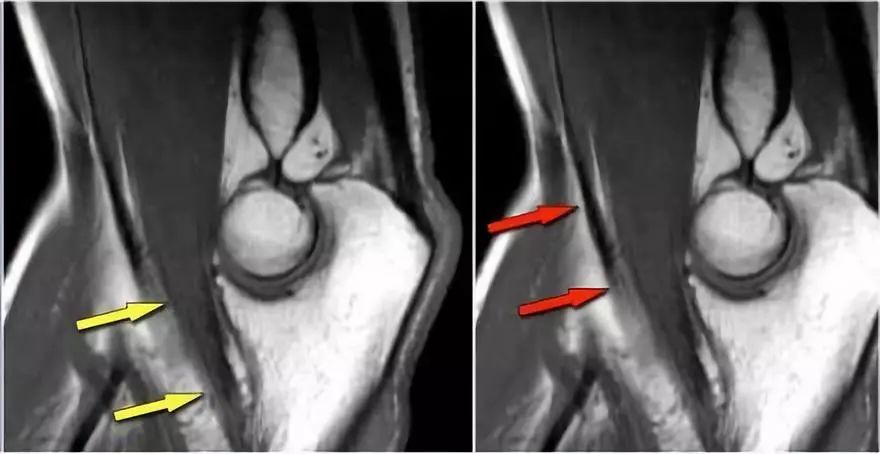

冠状图像上有一个美丽的UCL前束,但注意到关节内侧部分有骨赘形成(红色箭头)。当我们按照顺序向下看,可以看到存在一小部分低信号强度(黄色箭头),这是UCL的一部分撕裂。

当我们看轴向扫描时,我们可以欣赏巨大的骨赘形成。请注意,尺骨神经(蓝色箭头)紧邻这些骨赘,这些可能指示尺神经出现病变。